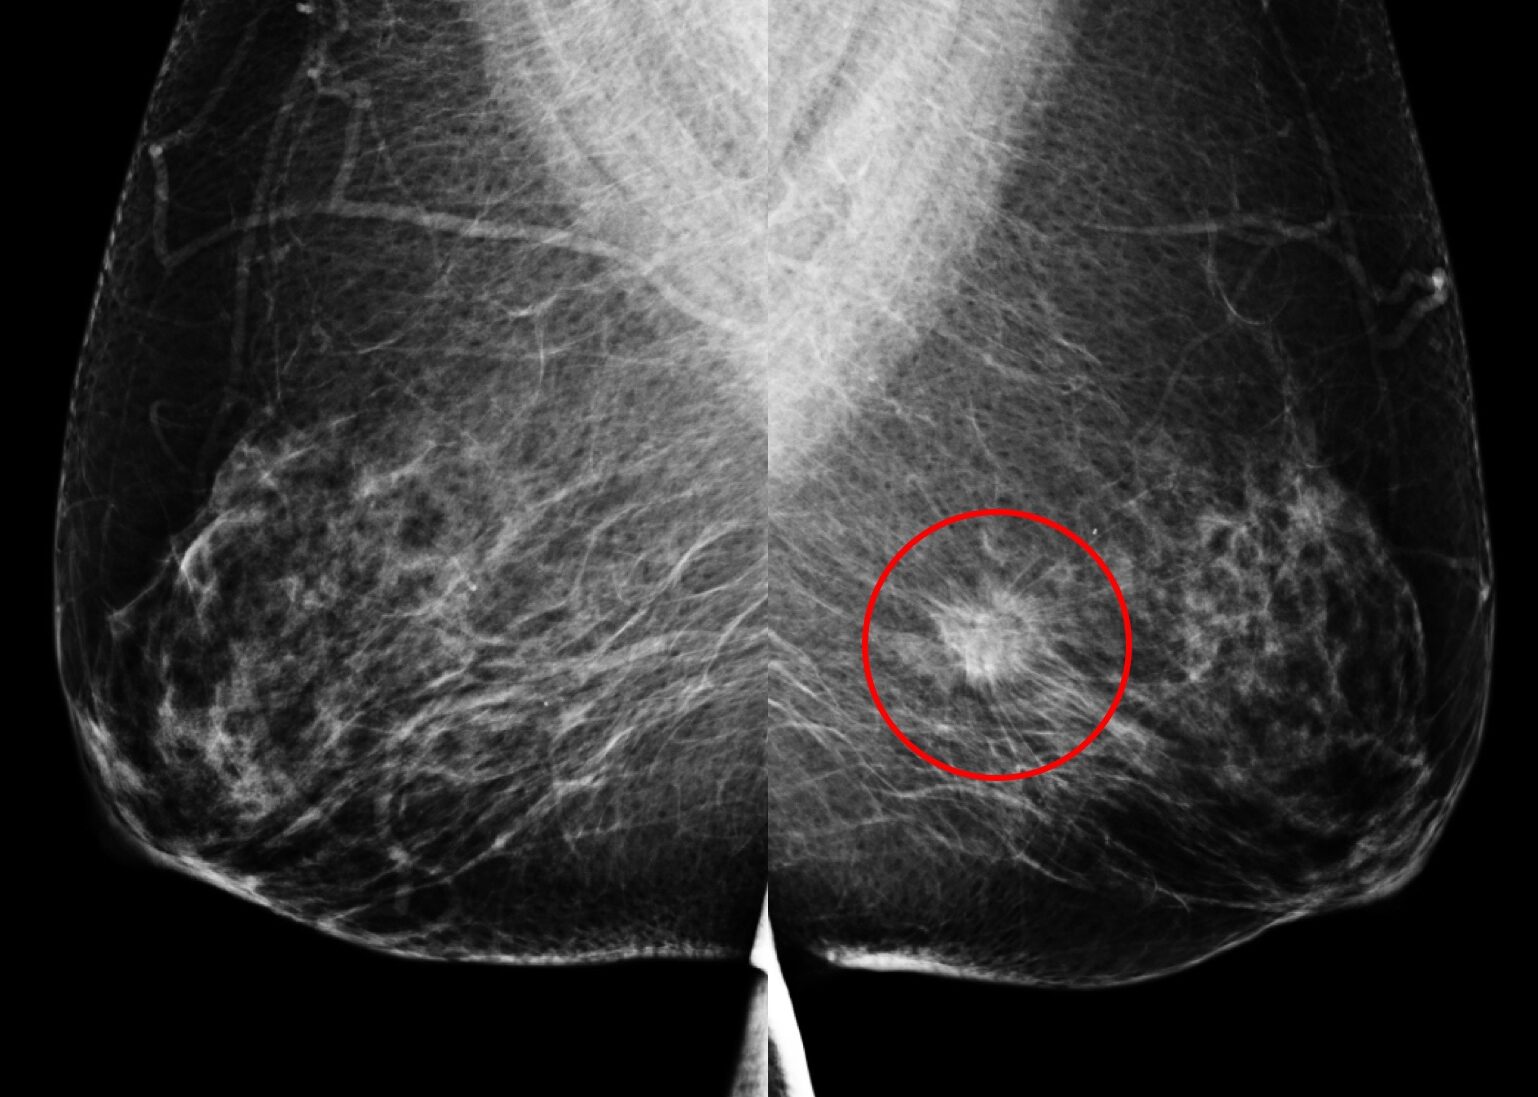

乳房X光攝影

(A) 61歲女性於國健署「乳房攝影篩檢」發現:左乳上方有一不尋常的群聚鈣化點、經手術證實為乳房原位癌,後續恢復良好。

另一名55歲女性於國健署「乳房攝影篩檢」發現:左乳下方有一局部腫塊合併組織變形,經切片證實為早期乳房侵襲癌。